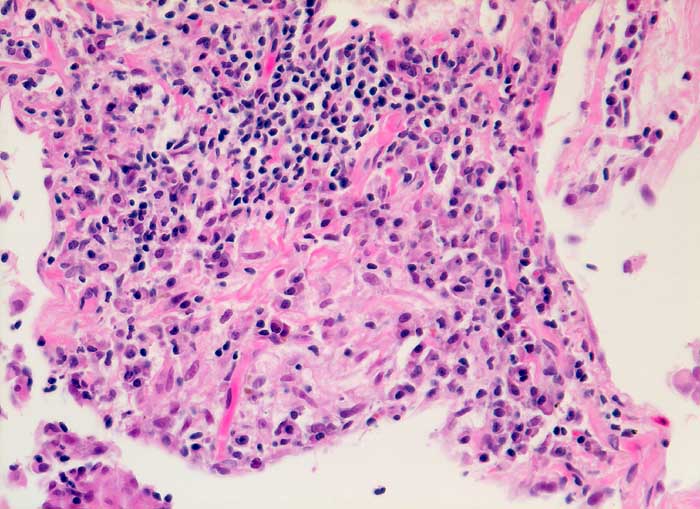

Exogen allergisch Alveolitis

Deutlich ausgeprägte interstitielle lymphoplasmozytäre Entzündung und lockerem intraalveolärem epitheloidzelligem.

Broncho-alveoläre Lavage: Massive Lymphozytose und deutliche Vermehrung der Alveolarmakrophagen mit schaumzelliger Umwandlung. Mässige Eosinophilie und deutliche Vermehrung der Mastzellen.

BOOP, Cordarone-Pneumopathie, Alveolarzell-Ca ?

Histologie

200